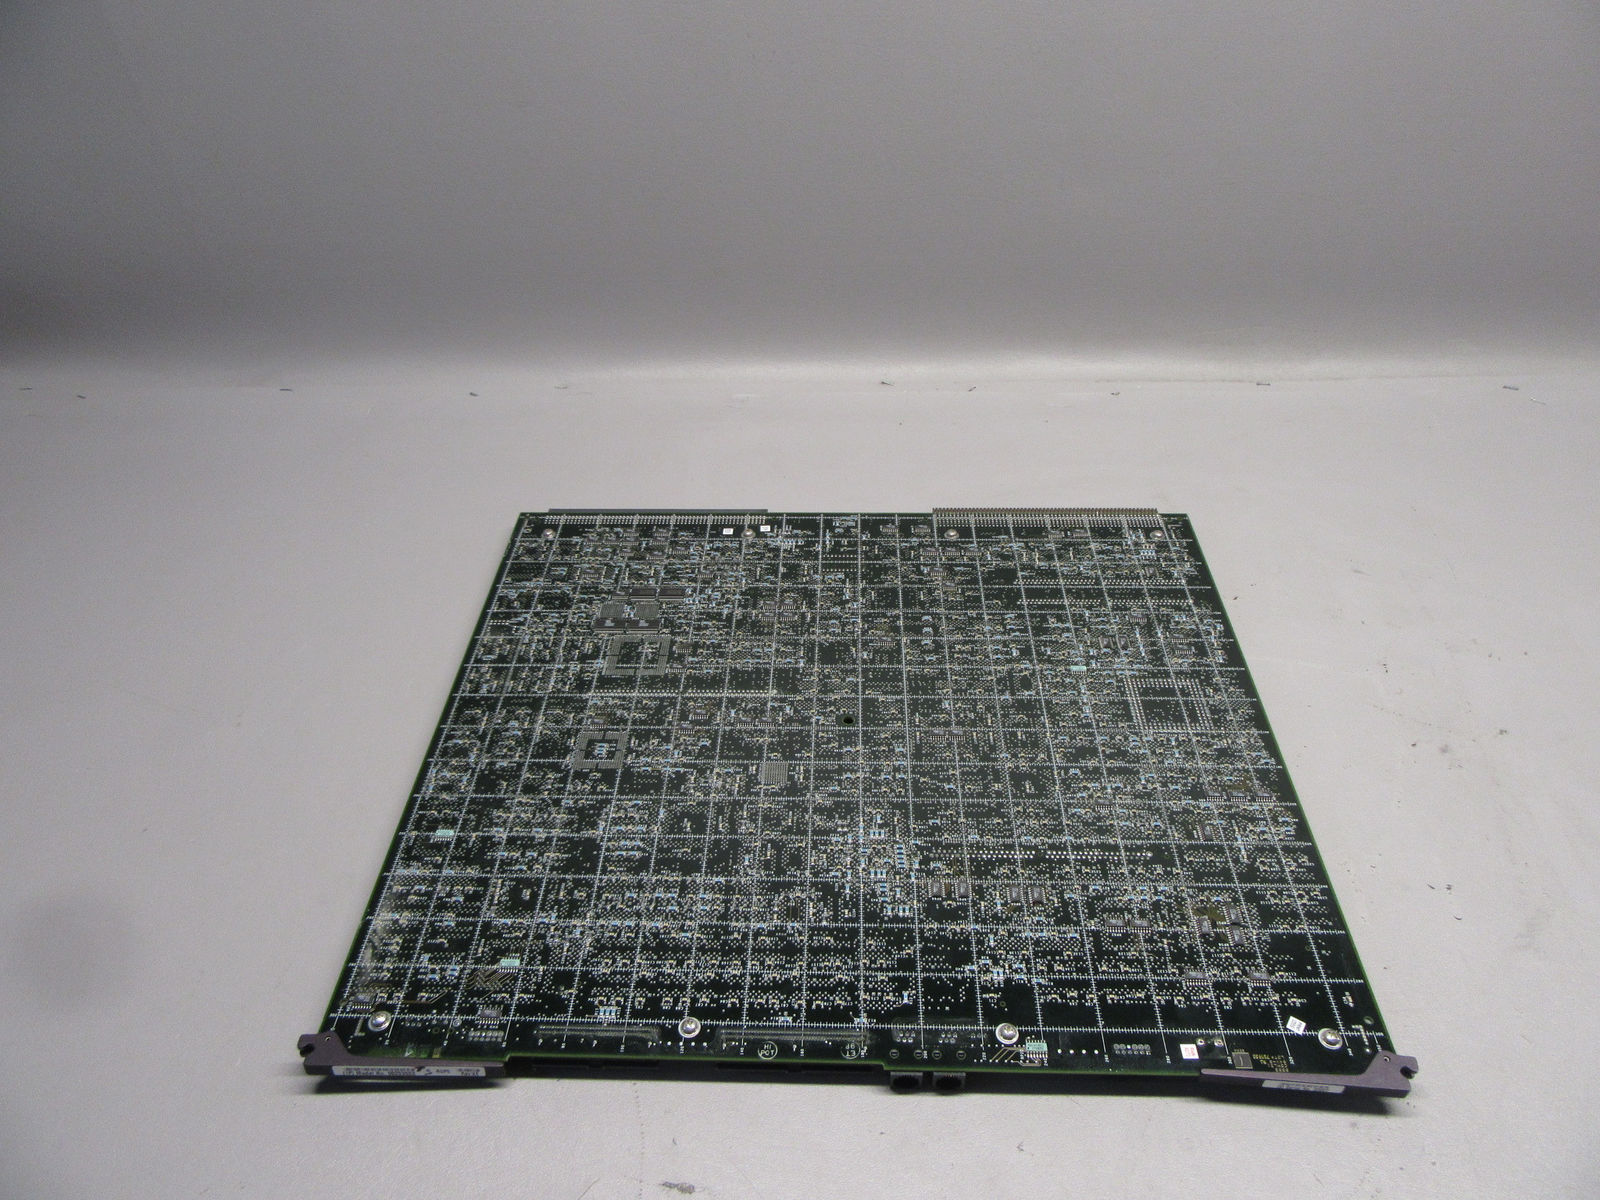

Acuson Probes

DIAGNOSTIC ULTRASOUND MACHINES FOR SALE